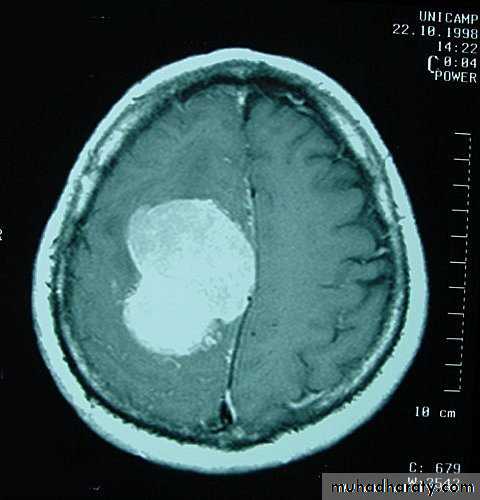

Meningiomas

• These account for 15% of intracranial neoplasms, and are the most common benign neoplasm.• They occur more frequently in women than in men, and their incidence peaks in middle age.

• The tumour arises from meningothelial cells of the arachnoid villi.

• They classically arise from a broad base along the dura.• They may invade bone.

• They derive their blood supply from the external carotid circulation.

• Malignant meningiomas are relatively rare.

• The symptoms and signs are related to those of intracranial mass lesions or seizures.

• CT scan accurately diagnoses the lesions.

• Complete surgical removal usually results in cure.

MeningiomaPre contrast CT

MeningiomaPost contrast CT

MeningiomaPre contrast MRI

MeningiomaPost contrast MRI